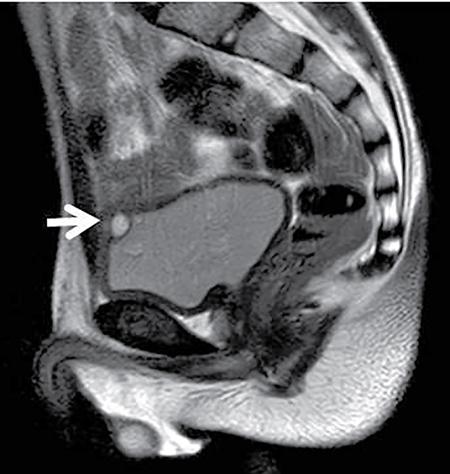

Anmol Bhatia, Kushaljit Singh Sodhi, Akshay Kumar Saxena Congenital as well as acquired anomalies of the bladder and urethra are a significant cause of morbidity in children. Various radiological investigations for imaging bladder and urethra include ultrasonography (US), voiding cystourethrography (VCUG) and intravenous urography (IVU), computed tomography (CT), magnetic resonance imaging (MRI) and contrast-enhanced voiding urosonography. In this chapter, we will discuss and illustrate a wide spectrum of congenital and acquired anomalies of bladder and urethral in children. Foetal allantoic stalk is the connection between the bladder dome and the umbilicus during the embryogenesis. Normally, it gets involuted by the second month of gestation. Depending on the degree of the persistence of this foetal allantoic stalk results in varying types of urachal remnants. The clinical presentation depends on the type of urachal remnant: Fluoroscopy is the best imaging modality for documenting the patency of urachus. However, there may be an underestimation of the exact length of the urachal remnant as inflammation occurring along the tract may block its lumen. CT and MRI are usually not needed for the detection of urachal remnants. However, urachal remnants are usually detected incidentally on CT scan done for other indications. Cystic or solid elongated tubular structure may be seen extending from bladder dome to umbilicus. A focal cystic lesion (Fig. 10.11.3) may be seen in the midline anywhere from bladder dome to umbilicus. In case the urachal remnant present with the symptoms, resection of the entire tract is warranted. Bladder diverticulum are localized outpouching from the bladder wall. They can be single or multiple of varying sizes. A male predominance is seen in comparison to females. It has been traditionally classified into four types: They can be incidentally detected or present with complications including recurrent UTI, urinary retention, incontinence, stone formation, VUR and bladder or ureteric obstruction. Bladder diverticulum should be differentiated from ‘bladder-ears’ in newborn male which is bilateral protrusion of bladder wall into inguinal ring. These are transient and disappear with growth. Appearance of diverticulum depends on cause, location, size and presence of complication features. VCUG under fluoroscopy is most efficient method to demonstrate diverticulum. Fluoroscopic monitoring during all phases including voiding and immediate postvoiding phase is important along with oblique and lateral views. Contained contrast-filled outpouching is seen which may be visible only during voiding phase when urine is forced into diverticulum during bladder contraction. Associated VUR is present in 50% of cases. Round or oval anechoic structure arising in communication with the bladder is seen. Well-defined homogenous structure with fluid attenuation/signal intensity arising from bladder wall (Fig. 10.11.6). Secondary complications like stone formation or rupture can be seen. Surgical removal using intravesical, extravesical or combined approach may be performed along with meticulous repair of bladder wall. Urinary bladder neoplasms are not commonly encountered in children. The majority of bladder neoplasms in children are of mesenchymal origin and overall rhabdomyosarcoma is the most common malignancy (Table 10.11.1). They can be incidentally detected or present with urological symptoms including dysuria, haematuria, incontinence and lower abdominal pain. It can manifest as filling defect in MCU studies done for other indications. Ultrasound is usually the first line investigation with cross-sectional imaging being performed in suspected cases for accurate characterization, localization, disease extent and complication. Histopathological analysis is often needed for final diagnosis. The differential diagnosis of bladder masses includes masses arising from adjacent pelvic structures, variants like ureterocoele or urachal remanent, mass forming cystitis (eosinophilic cystitis, BK virus–associated cystitis), haematoma, calculi or iatrogenic materials (e.g. Deflux used in VUR surgeries). Rhabdomyosarcoma Leiomyoma Neurofibroma IMT Leiomyosarcoma Angiosarcoma Haemangioma Urothelial carcinoma PUNLMP: urothelial papilloma Fibroepithelial polyp Paraganglioma Nephrogenic adenoma PUNLMP, papillary urothelial neoplasm of low malignant potential. Rhabdomyosarcomas are the most common urinary bladder neoplasms in first two decades of life presenting typically at ages 2–6 years and 15–19 years. Syndromic association with Li–Fraumeni cancer syndrome, NF type 1, MEN 2A has been found; however, majority are sporadic in origin. Histological subtypes include embryonal rhabdomyosarcoma (classical, botryoid and spindle cell variant), alveolar and undifferentiated sarcoma types of which embryonal form accounts for 90% of all cases. Locoregional spread to adjacent organs, muscles, regional lymphnodes is seen with distal metastasis to lung, cortical bones and retroperitoneal lymphnodes. Metastasis is found in approximately 10%–20% of patients at time of initial presentation. Overall survival and outcome depend on patient age and histological subtype with patients between 1–9 years of age and embryonal subtype having a better prognosis. Imaging work-up includes CT or MRI pelvis for local disease characterization and extent, CT chest, bone scintigraphy or FDG-PET for metastasis and staging. They commonly arise from bladder trigone and neck area. Ultrasound: They are typically large, intraluminal, multilobulated masses with well-defined margins and homogenous hypoechoic or hyperechoic echotexture. Foci of necrosis or haemorrhage are often seen. Vascularity on colour Doppler is increased. Hydronephrosis and bladder neck obstruction secondary to mass can be found. CT: Bulky heterogenous low attenuation mass that may invade into periurethral or perivesical tissue (Fig. 10.11.7). Calcification is rare.